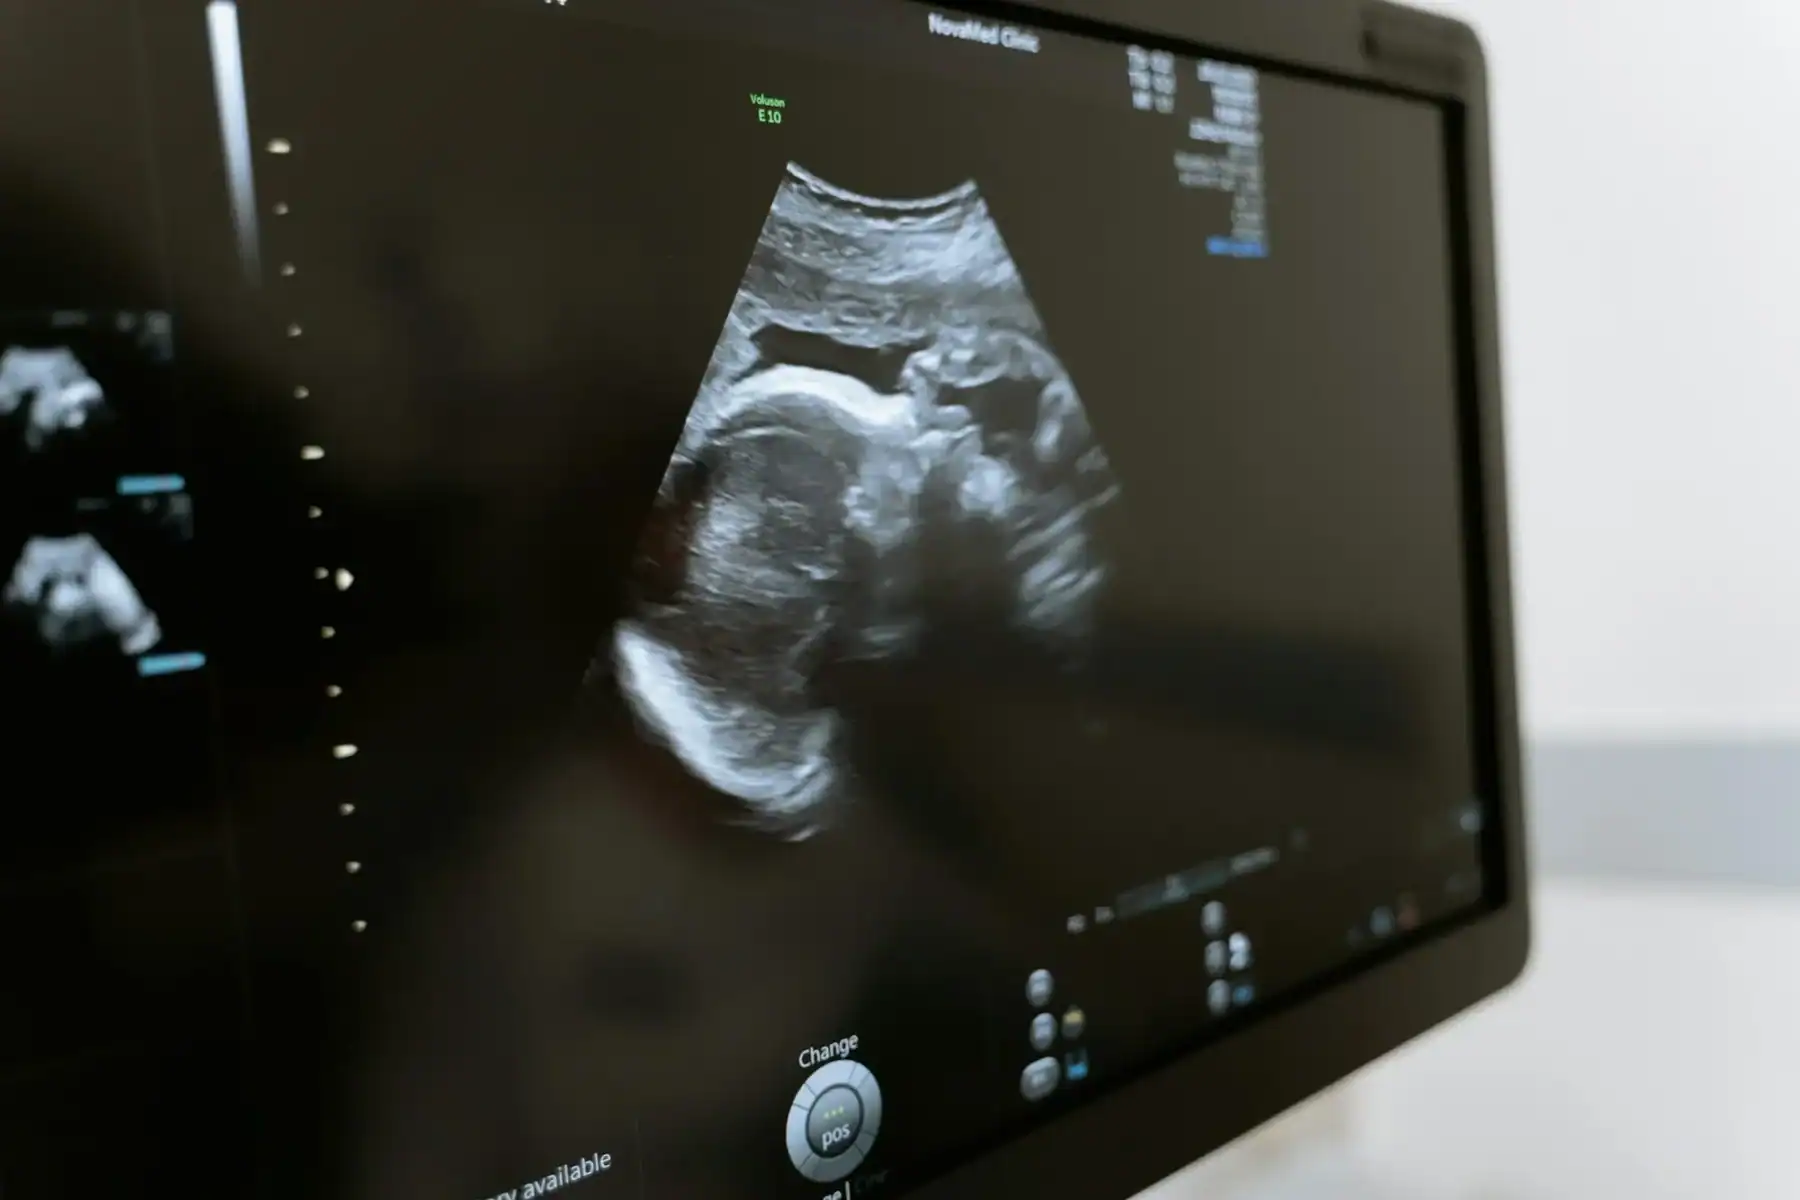

An ultrasound exam is a non-invasive diagnostic procedure performed by trained imaging professionals. During the appointment, a handheld device called a transducer is used to send sound waves through the body to create real-time images. The process is designed to be comfortable and typically does not require significant time or recovery afterward.